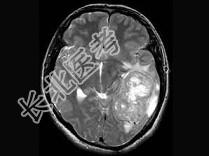

单项选择题女,34岁, 头痛数年,头颅MRI平扫及增强扫描, 最可能的诊断是 ( )

A、天幕脑膜瘤

B、星形细胞瘤

C、生殖细胞瘤

D、动脉瘤

E、三叉神经瘤